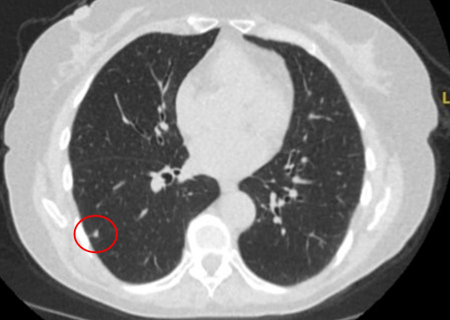

Nódulos com opacidade em vidro fosco: um crescimento de 2 mm no diâmetro máximo deve ser considerado potencialmente significativo, enquanto o desenvolvimento de um componente sólido sugere a necessidade de considerar uma investigação e/ou tratamento adicionais.[Figure caption and citation for the preceding image starts]: Tomografia computadorizada (TC) mostrando nódulo com opacidade em vidro fosco no lobo superior esquerdo. Este foi eventualmente ressecado após 2 anos de vigilância em decorrência de crescimento, e a histopatologia confirmou adenocarcinoma de pulmão com padrão mucinoso-lepídico mistoDo acervo de Dr. George Tsaknis, MD, PhD, FRCP (Londres), MRQA, MAcadMEd, PGCert; usado com permissão [Citation ends].